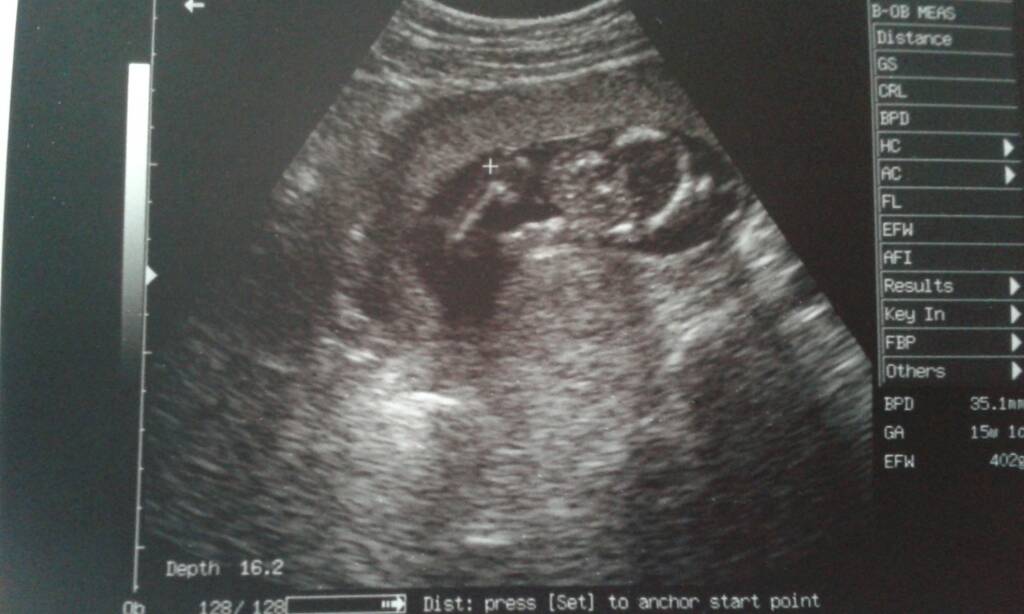

Aob moja wizyta nie była taka krótka, bo pokazała nam wszystko po prostu nie mierzyla, nie wazyla dzidzia Ani przeplywow itd nie sprawdzała, tętno tylko zmierzyła 154było. ba, nawet w 3D sobie popatrzylismy :D

uploadfromtaptalk1464978632761.jpg

A to Buzka naszej gwiazdy która prawie całe badanie miała stopu na czole i tylko na chwilę nam się pokazała :)